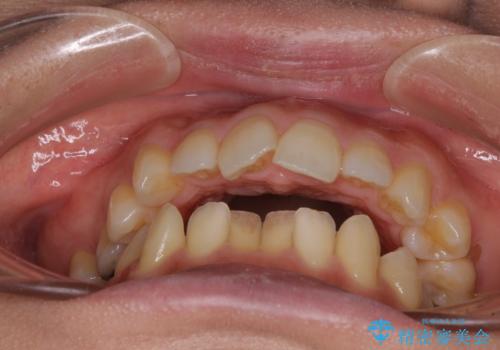

左上奥歯には乳歯が残存しており、後続永久歯は舌側に転位していました。

乳歯を抜歯し、舌側の永久歯を引っ張り出すこととしましたが、希望のインビザラインでは移動量が大きすぎて対応できない可能性があったため、ワイヤー装置にて改善することとしました。

ワイヤー装置にてある程度歯列が改善されたところで、上下をインビザラインにて矯正治療を行うこととしました。